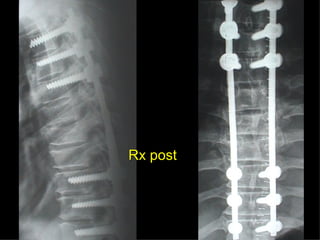

Rx post

Conclusioni Riduzione  anatomica Minimo trauma chirurgico Corretto equilibrio fra elasticità e stabilità Precoce mobilizzazione